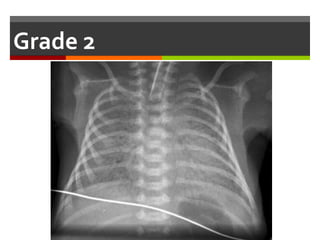

Findings can be graded according to the severity:

 Grade 1 (mild cases): the lungs show fine

homogenous ground glass shadowing

 Grade 2: widespread air bronchogram become

visible

 Grade 3: confluent alveolar shadowing

 Grade 4: complete white lung fields with obscuring

of the cardiac shadow

Chest x-ray:

Grade 1

Grade 2

Grade 3

Grade 4